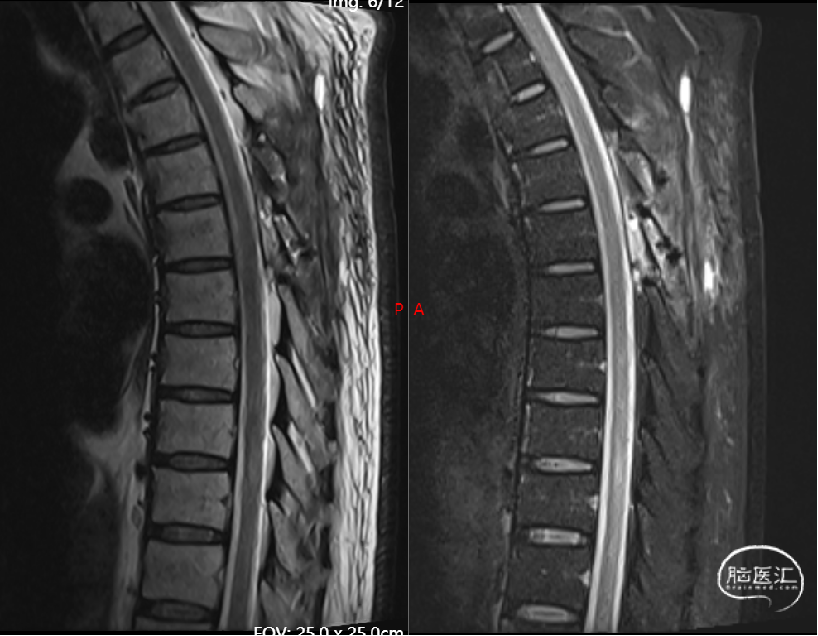

术前影像(2024-02-06, 省二院)

image.png

现病史摘要:缘于5月余前患者无明显诱因逐渐出现双下肢无力,走路时酸胀感,易疲劳,不能长距离行走,右下肢明显,晨轻暮重,无疼痛、肌肉萎缩和大小便异常,完善颈胸部MRI显示胸髓表面多发迂曲血管影,胸5-12椎体水平髓内异常信号。